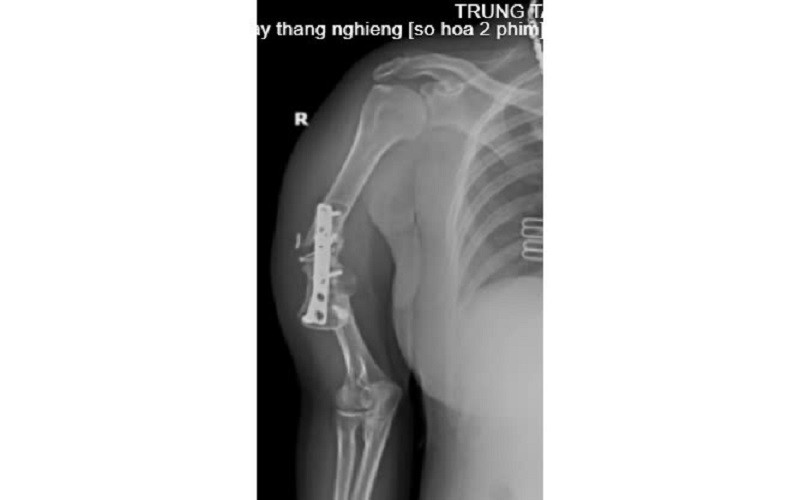

Cách đây 7 năm, sau một tai nạn, chị N.T.L bị gãy xương cánh tay phải, được phẫu thuật kết hợp xương bằng nẹp vít và mang theo phương tiện kết hợp xương kể từ ngày đó.

Năm 2023, chị N.T.L tiếp tục bị chấn thương vùng cánh tay phải nhưng không đi khám lại. Trong quá trình lao động và sinh hoạt hàng ngày, cánh tay phải của chị N.T.L dần bị biến dạng, gần đây vận động hạn chế và có cử động bất thường nên chị đã đến Trung tâm Y tế huyện Cẩm Khê để khám.

![]() |

Tình trạng bệnh nhân trước khi mổ. |

Sau khi thực hiện các cận lâm sàng, Bác sĩ kết luận: Khớp giả xương cánh tay phải/Còn phương tiện kết hợp xương, chỉ định phẫu thuật ghép xương điều trị khớp giả.